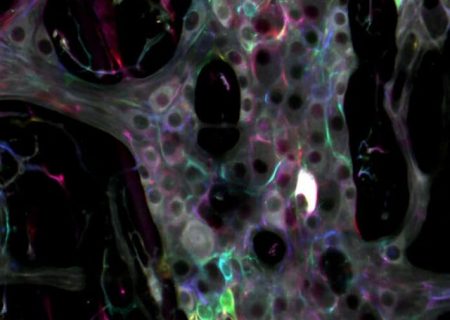

کشف حقایقی جالب درباره دومین مغز بدن

محققان دانشگاه ایالتی میشیگان اخیرا حقایق جالبی درباره سیستم عصبی روده(gut’s enteric nervous system) انسان کشف کردهاند.